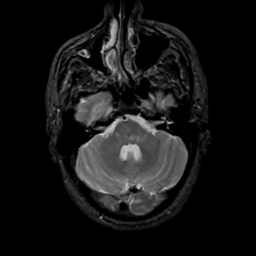

MR Study #14, June 2, 1991 -- Slice #12

[Home][Help][Clinical][Tour 1][Tour 2] Slice 12